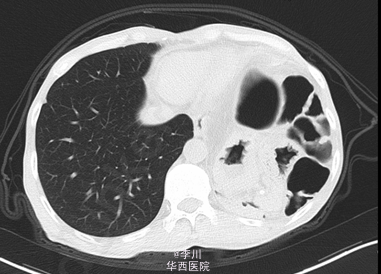

患者男,49岁9月,因“ 全腹胀痛14天,加重伴呕吐4天”入院。患者14天前在进食“甜酒”后出现腹部胀痛,逐渐扩大到整个腹部,伴恶心干呕,不伴寒战发热、腹泻、晕厥,无心悸、气促、发绀。外院诊断“肠梗阻”,予以石蜡油灌肠及输液治疗后缓解。4天前患者在进食后出现同前症状,遂于我院就诊。

既往患者1+年前因摔跤撞伤腹部,于贵阳医学院行“脾切除+膈疝修补术”。查体左肺呼吸音减弱,可问及异常肠鸣音。CT提示:左侧膈面上抬、局部膈肌软组织似不连续,可见胃及部分肠管上移,膈疝?

在全麻下经左胸膈疝修补、胸膜粘连烙断、胸腔闭式引流术。术中发现:左膈肌外侧缺损约15cm×12cm大小,腹腔内网膜、胃及横结肠等组织疝入胸腔。网膜、胃、结肠组织与膈肌、胸壁片状粘连。左侧肺与胸壁广泛粘连。术后予抗炎、化痰、对症等治疗后好转。